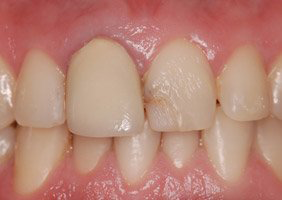

Cas 3 : Couronne toute céramique sur inlay-core céramisé et facette céramique sur deux incisives centrales chez un homme

La réalisation concomitante avec la même céramique usinée sur deux incisives centrales supérieures d’une couronne céramique sur dent dépulpée et d’une facette sur dent vivante permet d’optimiser le rendu esthétique du sourire